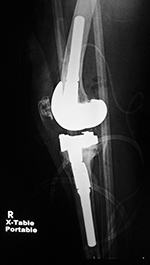

| Biomet XPA Bicruciate Preserving total knee arthroplasty |

Biomet Vanguard 360 Revision Knee System |

| 67 year-old woman. A surgical drain is present from recent surgery. From Taljanovic, 2005 |

This replaced a loose prior total knee arthroplasty. The patellar button was left in place. A surgical drain is in place, and there is subcutaneous gas from the recent surgery. |